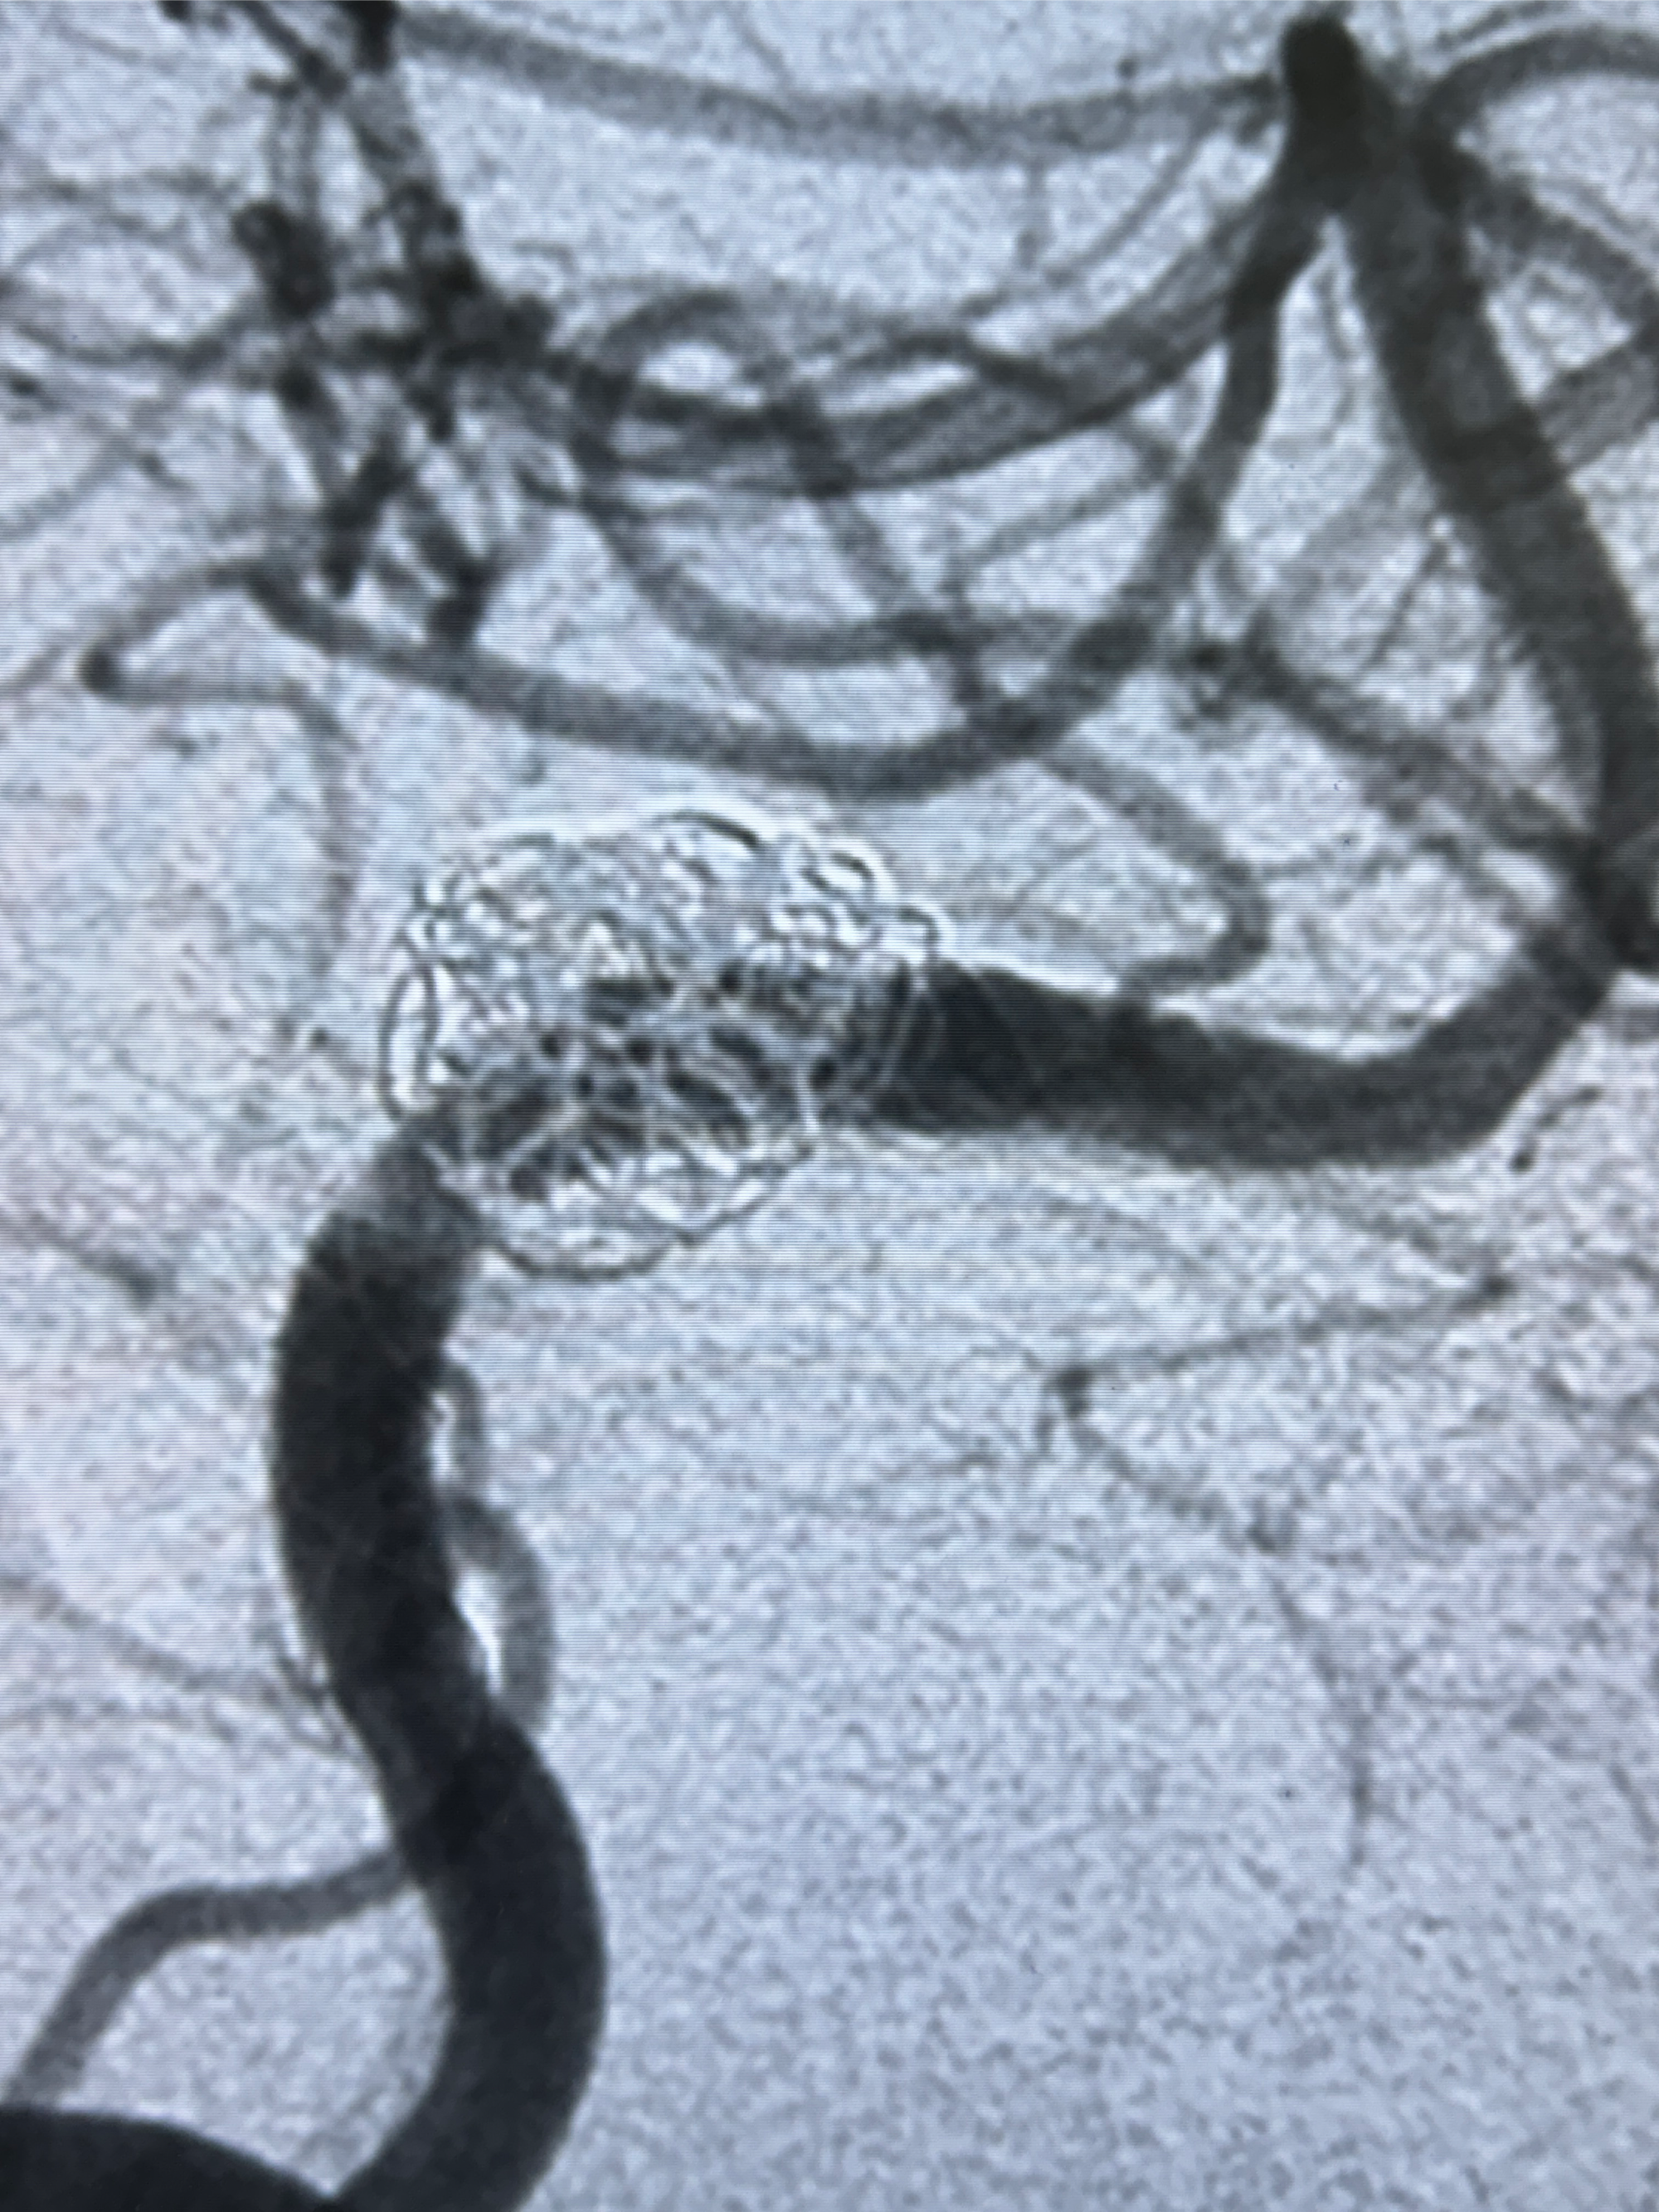

2024-01-08DSA:右侧椎动脉V4段夹层动脉瘤双支架辅助弹簧圈栓塞术后

患者支架辅助治疗后18个月,动脉瘤痊愈